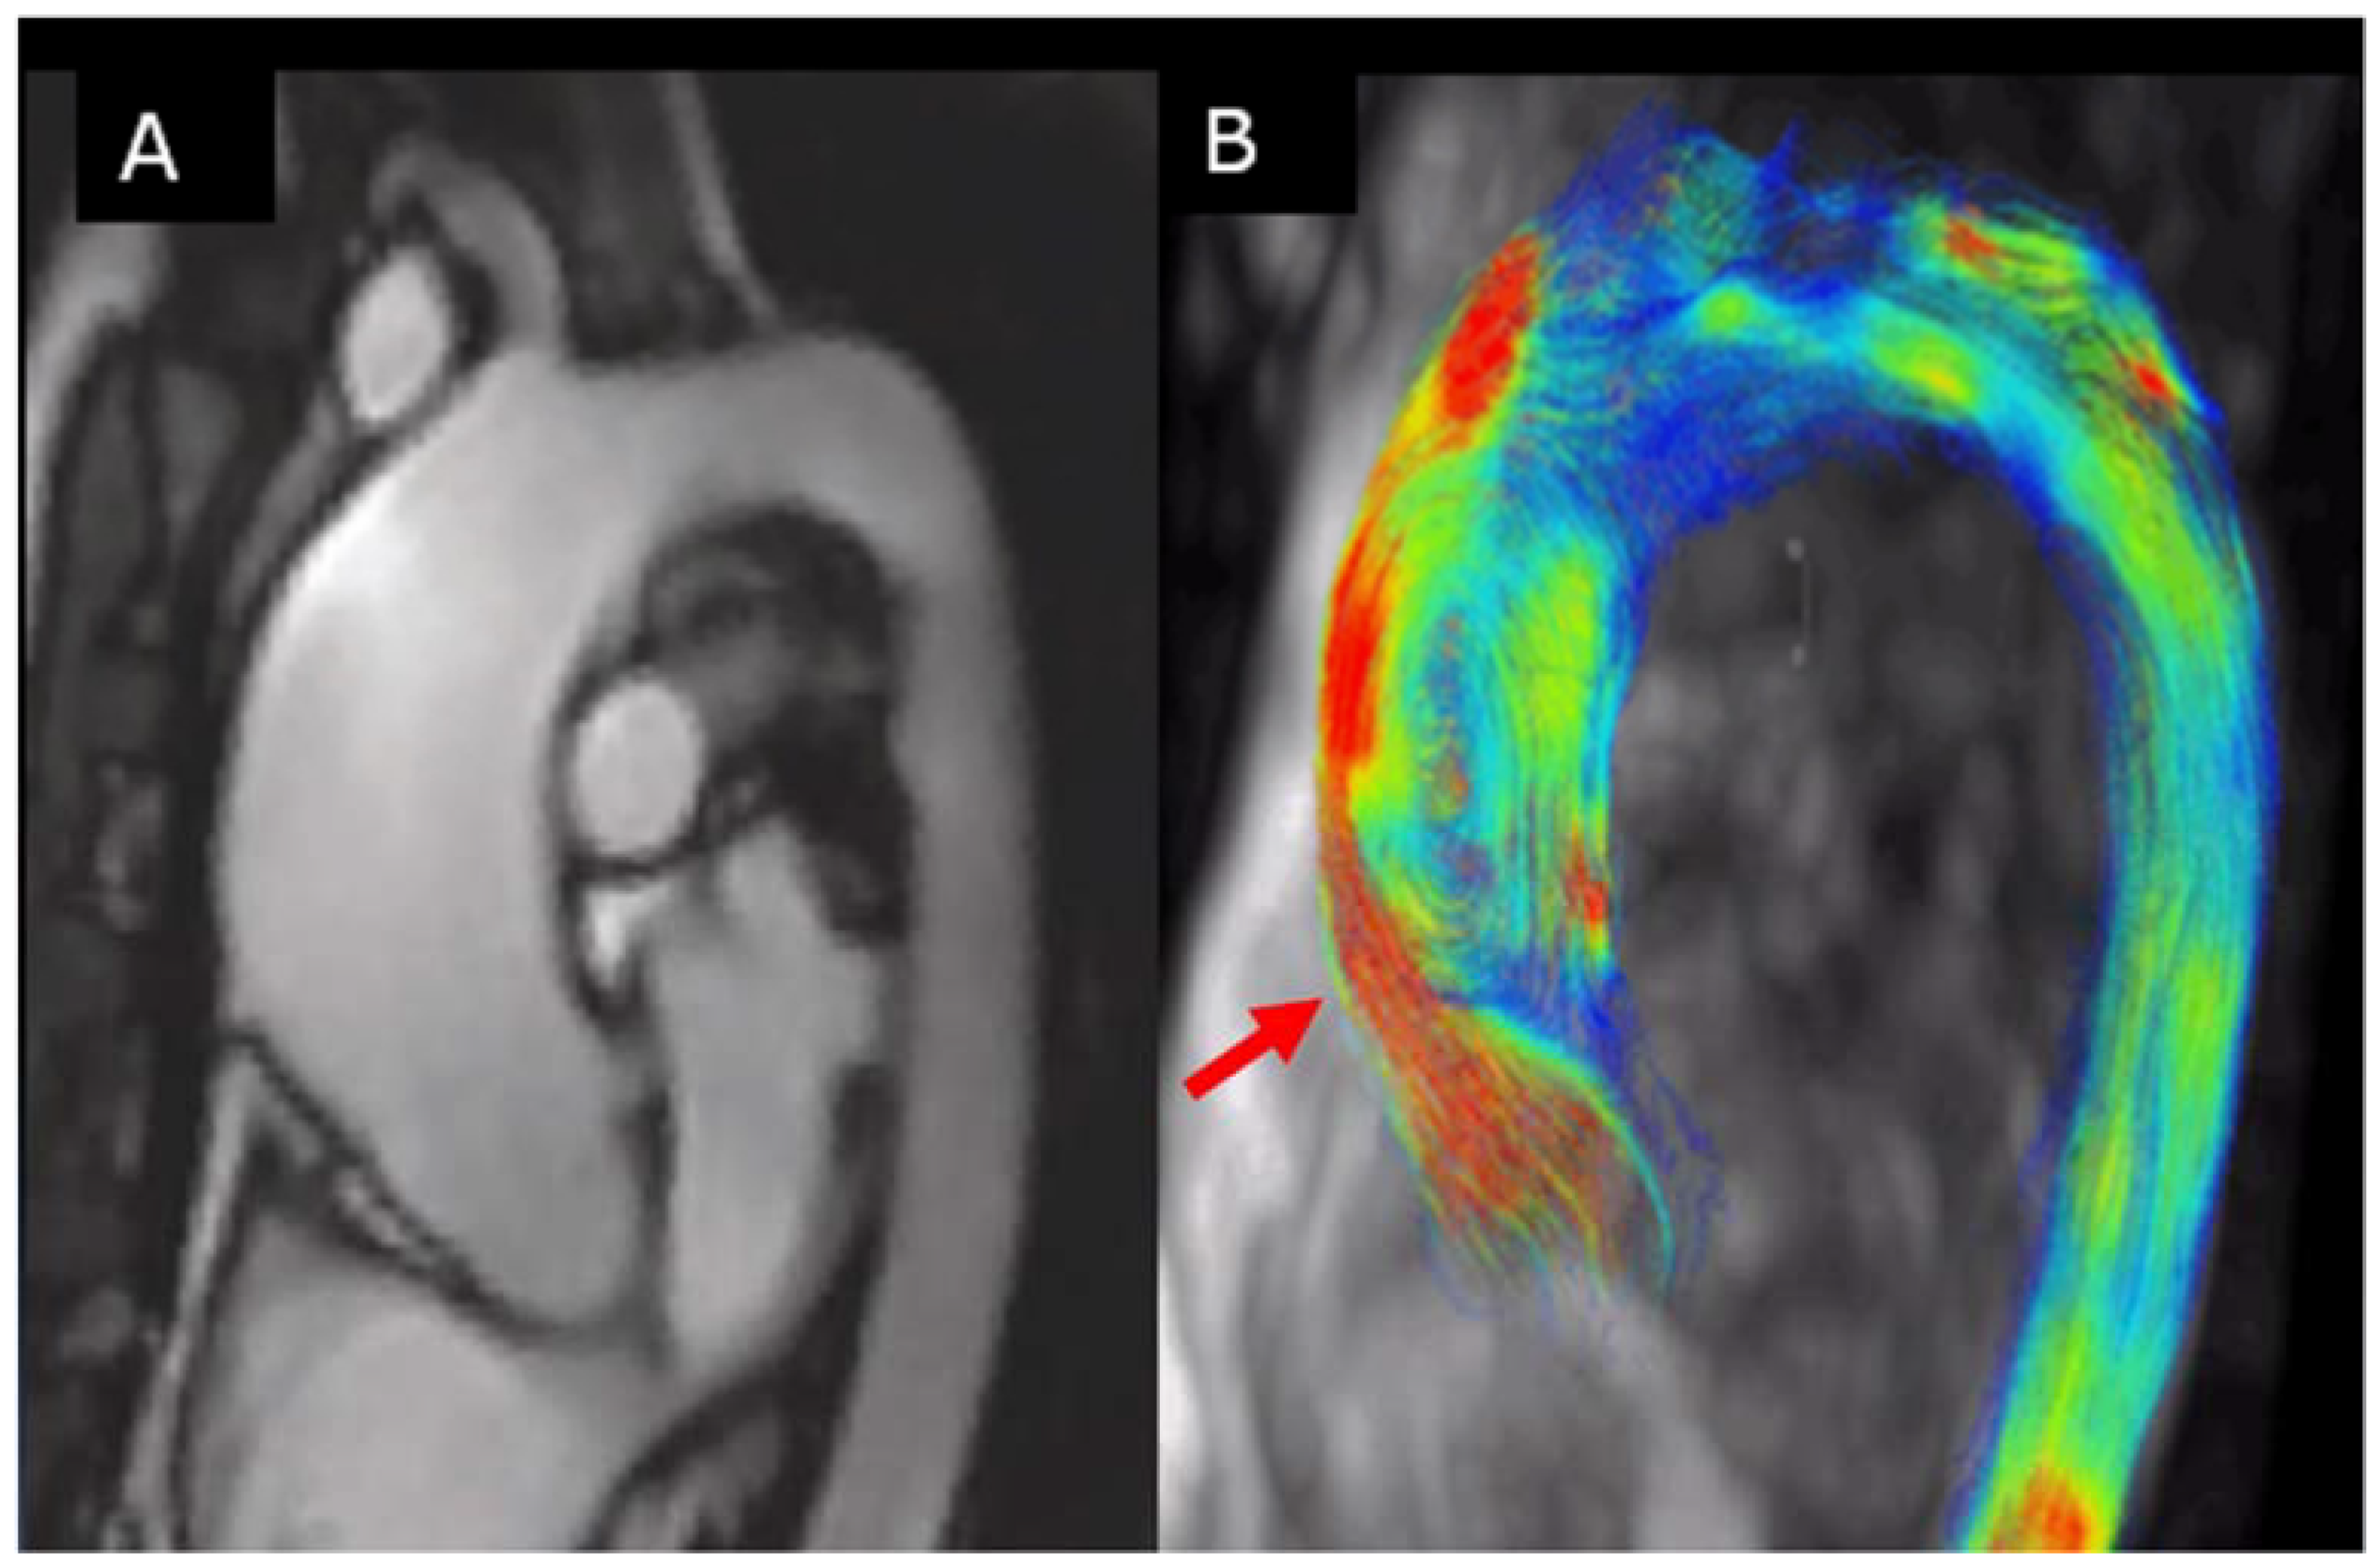

4D-flowCMR is very useful in the evaluation of abnormal ascending aorta flow in BAV patients (Figure 8). Several studies have shown the flow in the aorta of BAV patients to be eccentric, not directed in the same direction of the aorta [60,61,62,63]. Such flow abnormalities, also reported in non-dilated aortas, are thought to produce changes in wall shear stress (WSS), the force per unit of area exerted tangentially by blood on the aortic wall, which is associated with elastic fiber degeneration and extracellular matrix dysregulation [64]. The 4D-flow MRI shows different local flow abnormalities associated with the different leaflet fusion patterns [60] in particular, unlike at the ascending tract, where average systolic wall shear stress with BAV-RL and BAV-RN reached similar magnitudes. Higher shear stress values were found at the more proximal tract of the aorta with BAV-RL. However, the RN morphotype spared dilation at the root level and showed higher in-plane shear stress in cross sections at the tubular distal level. Interestingly, partial aortic valve leaflet fusion, a forme fruste BAV, may alter aortic flow patterns and may lead to aorta dilation [22,65]. In a longitudinal study, our group proved that in patients with BAV without significant valvular dysfunction, circumferential wall shear stress component independently predicted progressive dilation of the ascending aorta. Notably, mapping of WSS further allowed for establishing ascending aorta regions with the fastest dilation rates [66].

Figure 8.

(A) Thoracic aorta by CMR images of BAV with RC−LC fusion; (B) 4D-MRI dimensional flow. Note that flow impinges on the outer curvature of the proximal ascending aorta (arrows), including the root (red arrow).